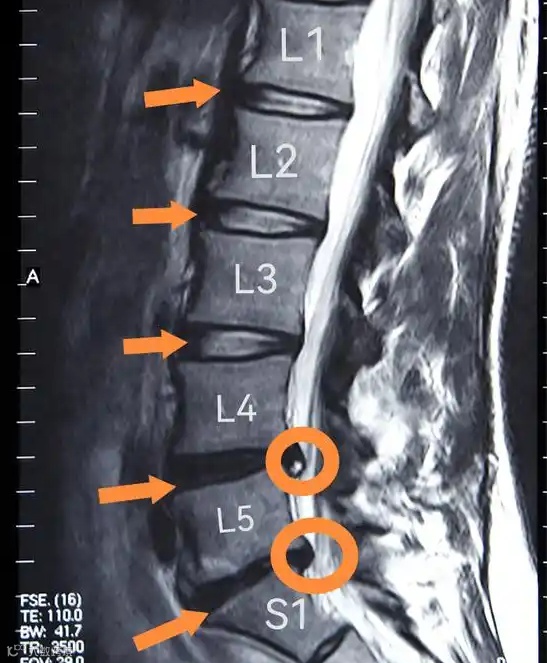

在健康管理中心,医生将详细询问你的工作习惯、日常活动,了解疼痛的具体部位、程度、发作频率等信息。接着,通过体格检查,测试颈部、腰部的活动范围、肌肉力量和神经反射。通过影像学检查,如 X 光、CT 和磁共振成像(MRI),能清晰呈现脊柱的骨骼结构、椎间盘状态和神经受压情况,为后续的个性化治疗方案提供关键依据,就像侦探破案一样,不放过任何一个细节,精准定位疼痛根源。